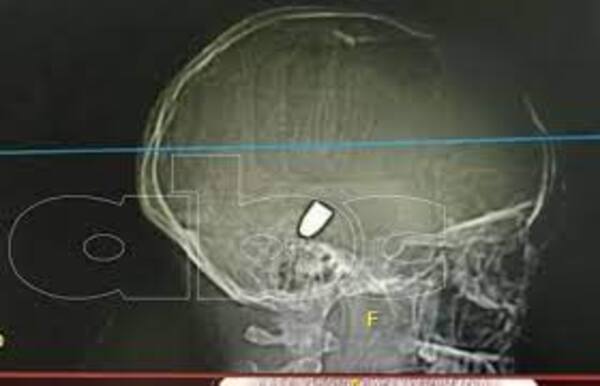

Niña víctima de bala perdida en PJC evoluciona favorablemente

Este sábado, los padres de la niña de 13 años que fue víctima de una bala perdida en Pedro Juan Caballero explicaron que su hija va evolucionando favorablemente y va despertando gradualmente. La paciente sigue internada en el Instituto de Previsión Social (IPS) y continúa en terapia por la gravedad del impacto. ...[Leer más]